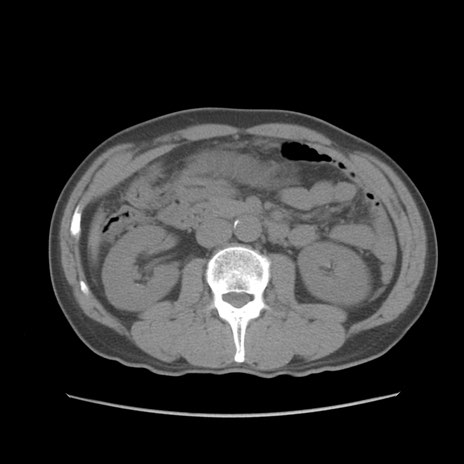

症例56 CT(横断像)

脂肪ウインドウ